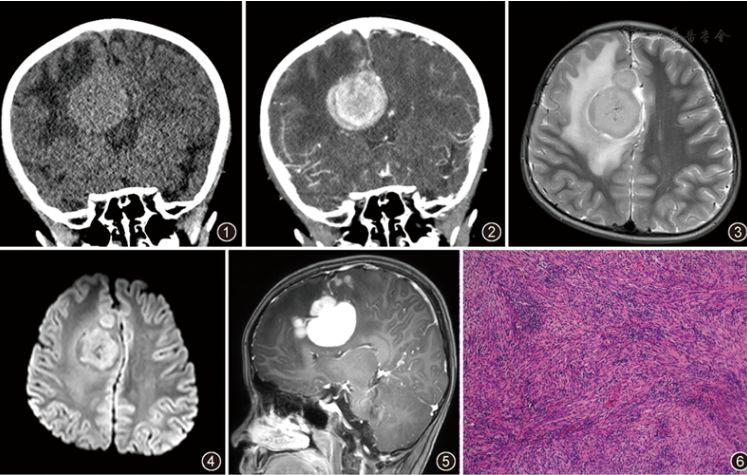

【病例报告】儿童右额叶炎性肌纤维母细胞瘤一例

图片尺寸747x475